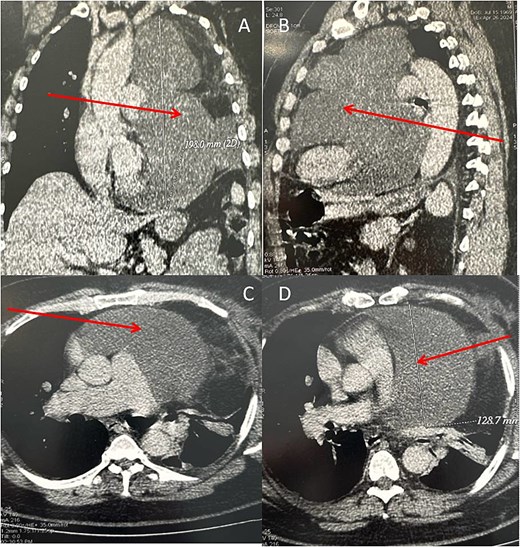

Because of the patient’s very poor echogenicity, TTE was unable to provide useful information, unlike thoracic computed tomography (CT), which revealed a mass of fluid density and homogeneous content, developed in the left pericardium and measuring 185 mm in height, 120 mm in transverse diameter and 140 mm in antero-posterior diameter. This mass compressed the left lung, which was reduced in volume, and displaced the heart chambers to the right (Fig. 2).

Chest CT scan (A: coronal section, B: sagittal section, C and D: axial section) in spiral mode with injection of contrast agent showing a giant pericardial mass (arrows).

This case is unusual in that it measures 185 mm in height, 120 mm in transverse diameter, and 140 mm in anteroposterior diameter, with a historical weight of 4200 g. There is no cardiac tumour, either intracavitary or pericardial, with these measurements. Soltani et al. reported a case of myxofibrosarcoma of the LA measuring 80/60/20 mm [2]. Kwon et al. reported a case of a rapidly growing undifferentiated sarcoma of the pericardium, which grew from 37/95 to 80/150 mm in 3 months and was also fatal to the patient in the setting of heart failure and arrhythmias [8]. Other authors have reported pericardial lipomas measuring 120/120/80 and 40/100 mm, respectively [9, 10]. All these reported cases present relatively exceptional measurements, but they remain smaller than those of the case reported here.